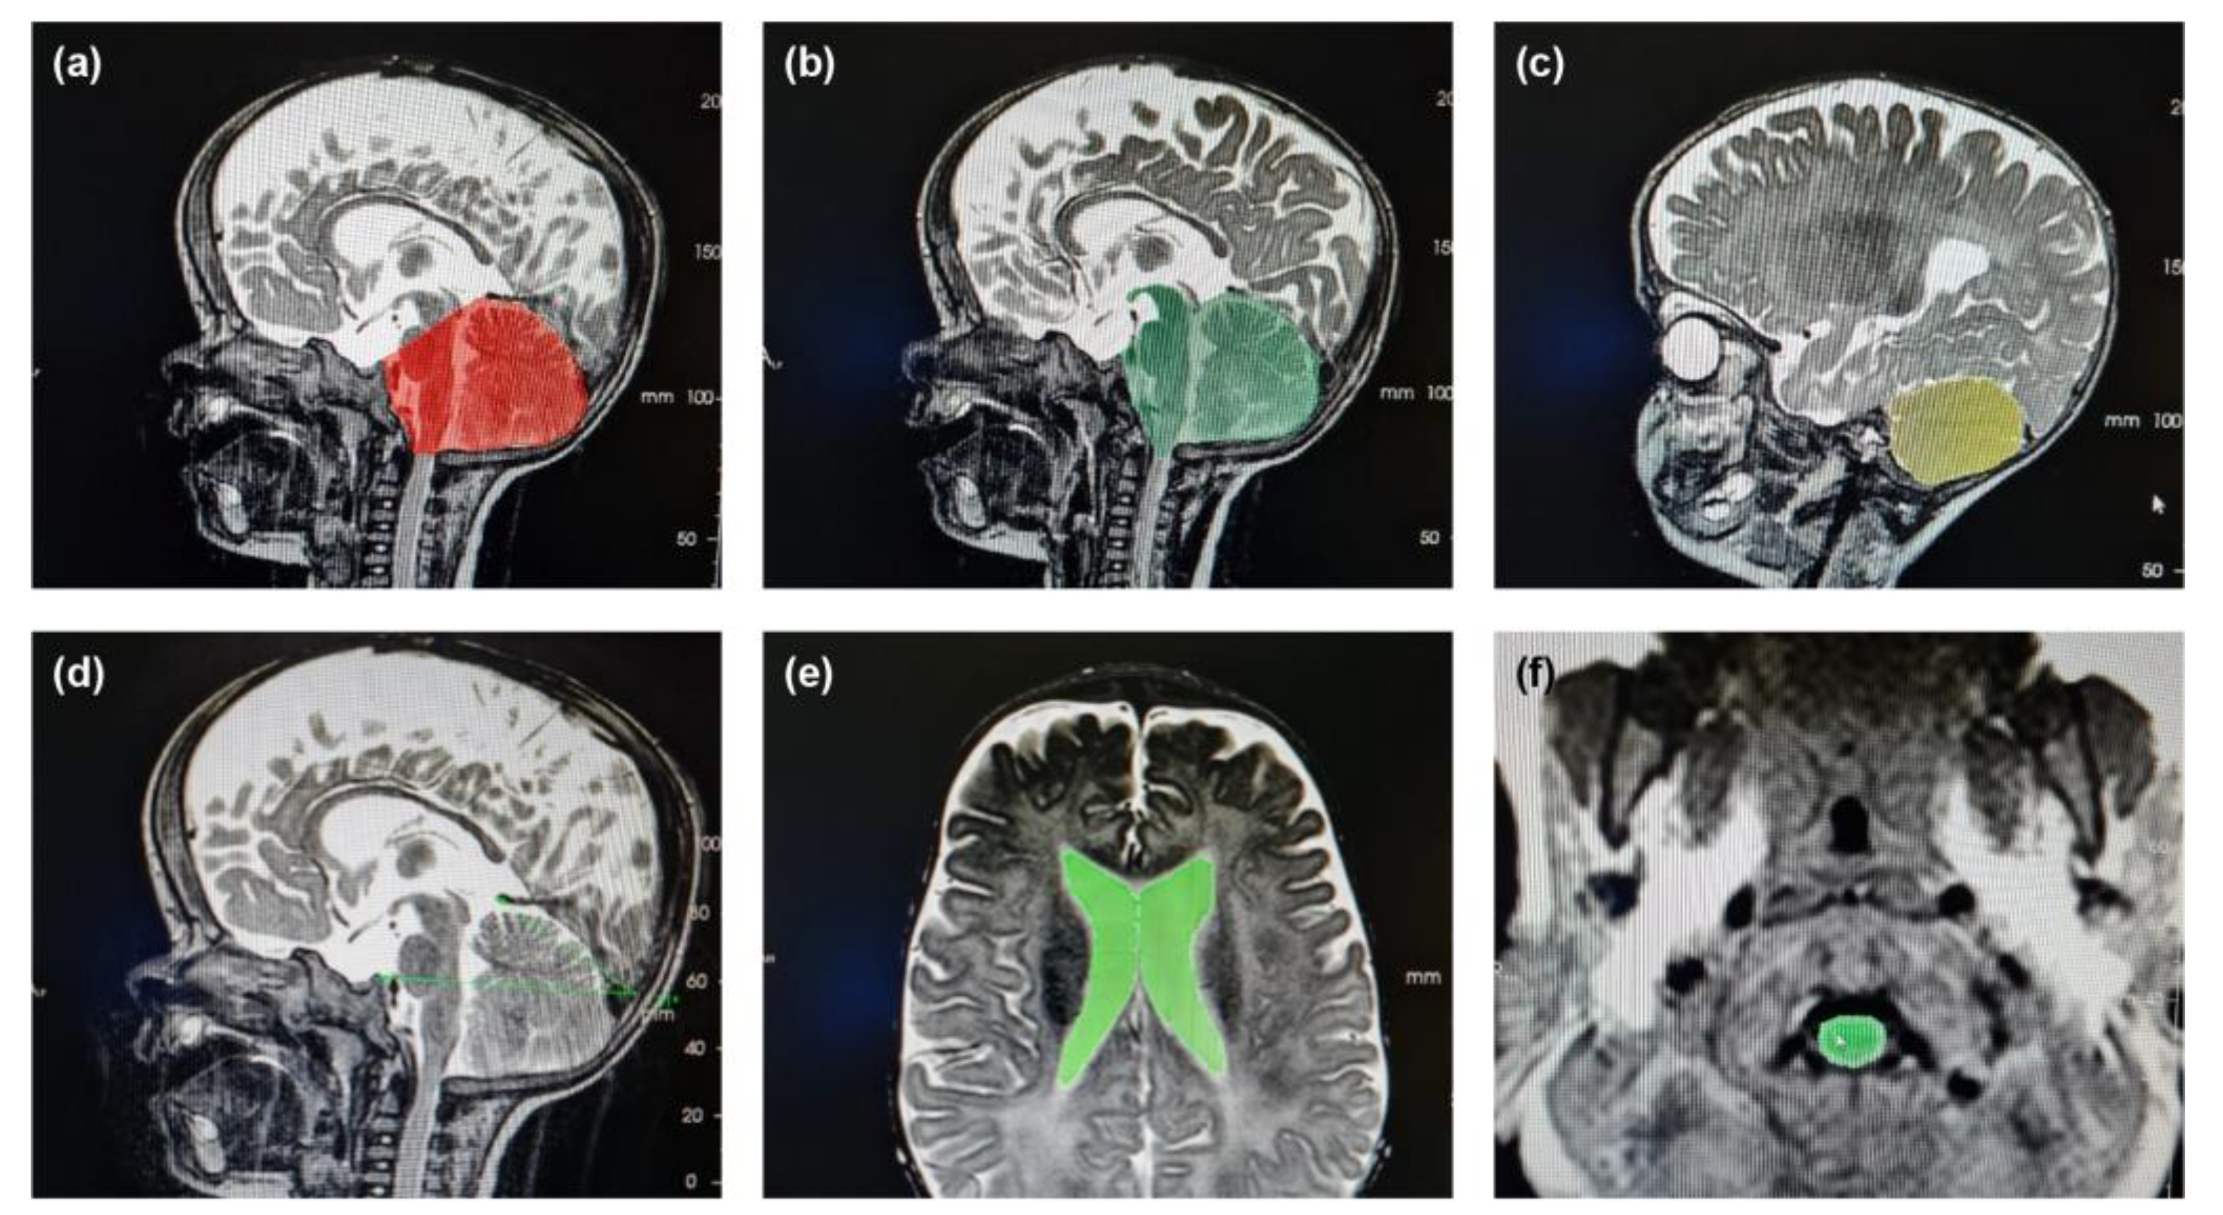

Illustrative examples of key anatomical structures on MRI scans from children with achondroplasia are shown in Figure 1. Of the 12 parameters measured and analyzed from the MRI scans, 10 showed significant differences between the achondroplasia and reference groups (Figure 2; Table S1). The diameter (mean 10.0 mm vs. 16.1 mm; p < 0.001) and area (mean 109.0 mm2 vs. 160.8 mm2; p = 0.005) of the foramen magnum were significantly smaller in children with achondroplasia compared with the reference group. Furthermore, the myelon area was significantly smaller (mean 40.6 mm2 vs. 47.7 mm2; p = 0.004) and the clivus significantly shorter (mean 23.5 mm vs. 30.3 mm; p < 0.001) in children with achondroplasia. The tentorium angle was significantly steeper in children with achondroplasia (mean 47.6 degrees vs. 38.1 degrees; p < 0.001) and was accompanied by a larger volume of “overhang” of the brainstem from the posterior cranial fossa (mean 4542.5 mm3 vs. 2614.4 mm3; p < 0.001). A significantly smaller volume of the fourth ventricle (mean 749.9 mm3 vs. 1056.2 mm3; p = 0.029) and corresponding significantly larger volume of the supratentorial ventricular system (mean 42,062.3 mm3 vs. 13,389.2 mm3; p < 0.001) was also observed. No significant differences between the achondroplasia and reference groups were observed in posterior fossa or cerebellum volume.

Figure 1. Illustrative examples of selected anatomical structures on magnetic resonance imaging (MRI) scans of children with achondroplasia. Shown are images used to calculate the following parameters: (a) posterior fossa volume, (b) proportion of brainstem volume outside the posterior fossa, (c) cerebellum volume, (d) tentorium angle, (e) supratentorial ventricular system volume, and (f) fourth ventricle volume.